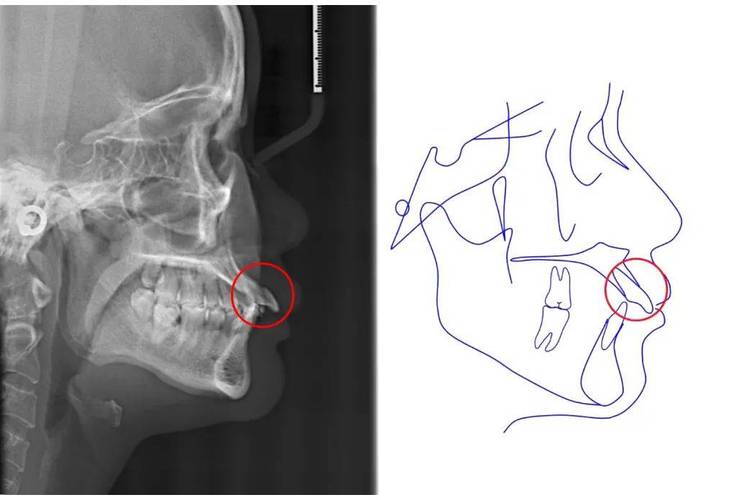

- X线片:薛氏位片(髁突-关节窝侧位像)观察髁突在关节窝内的位置;曲面断层片评估全口牙列与颌骨关系。

- CBCT:三维重建关节结构,精确测量髁突位置、关节窝形态及骨质变化。